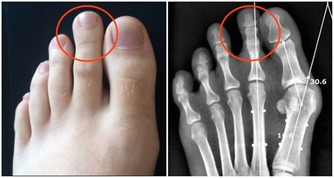

*****(3)腎病的人。*****

洋蔥中含有較高含量的磷元素,而吃多了元素,就會加重腎臟的負擔,這不僅不利於疾病的康復,還有可能因為攝入過量的磷無法處理而造成別的不良後果。因此,腎病的人最好不要吃洋蔥。如果真的想吃,可以把切開的新鮮洋蔥放到活水中沖洗十分鐘或者以上,以沖掉磷元素,這時候腎病的人就能吃這些處理過的洋蔥了。